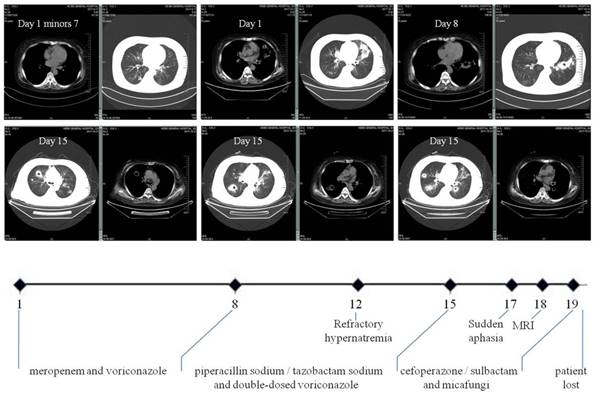

Figure 1

Clinical course of our case. It schematically recorded the selection of antibiotics according to the dynamic changes of CT images and the accompanying complications. In particular, multiple polysized pulmonary nodules with cavitation at different levels were highlighted (both parenchymal and mediastinal windows). The numbers on the X axis denote the day from the admission (Day 1) to the loss of patient (Day 20).

Readmission occurred seven days post hoc due to fever (38.6°C) and hemoptysis. CT scan on admission (Day 1) found PI with cavitation. Laboratory tests showed WBC count 20.3×109/L with 96.9% neutrophils, T-lymphocyte count 102/uL (690-1760/uL), hemoglobin 110g/L (130-150g/L), platelet 170×109/L (100-300×109/L), C-reaction protein 185.2mg/L (<10mg/L), calcitonin 1.6ng/mL (<0.05ng/mL), (1,3)-β glucan D detection test (G-test) 67.8pg/mL (<10pg/mL), serum creatinine 300.0umol/L, normal coagulation function including D-dimer and negative ANCA. Aerobic sputum but not blood cultures produced aeruginosa. She was immediately given intravenous broad-spectrum antibiotics with dose and form respectively determined by creatinine clearance and CT findings (Figure 1): meropenem and voriconazole (Day 1 to 8), piperacillin sodium/tazobactam sodium and voriconazole with double-dose (Day 9 to 14), cefoperazone/sulbactam and micafungi (Day 15 to 19). The use of steroid was continued but reduced to half-dose two days after admission. Meanwhile, recurrent hypernatremia emerged (150-170mmol/L) which was only remedial to blood purification. There was sudden aphasia and right hemiparesis, prompting the collection of blood and sputum from deep trachea for specific microbial tests by our pharmacological center, which is a reliable and sophisticated research institution [24,25]. In short notice thereafter, brain abscess was detected by MRI (Figure 2). The patient's condition further worsened and her vitals were no longer sustainable (Day 20). After that, growth of Nocardia asteroids from the said sputum was found on the Loewenstein-Jensen media and subsequently confirmed by the 16S rDNA sequence analysis [26].

The body site most frequently involved was the lung accounting for 70% of the infection, followed by the skin and the brain [27]. Pulmonary involvement may manifest fever, cough and hemoptysis, with pleomorphic radiographical findings of infiltration (62.6%), multiple nodules (31.3%) and cavitations (18.8%) [20] (Figure 1). Accordingly, the main differential diagnosis includes invasive fungal disease, Wegener's granulomatosis, malignancy, alveolar hemorrhage in ANCA-associated vasculitis and tuberculosis. As priori, invasive pulmonary aspergillosis may demonstrate the characteristic halo sign on CT scan (Figure 3A and B) and a definite diagnosis is supposedly possible in the later course of infection (clinical symptoms and signs >10 days) with elevation of the G-test [28]. By comparison, pulmonary nodules in Wegener's granulomatosis were usually well demarcated and distributed mainly in the peripheral zone on CT scan (Figure 3C and D) [29]. Of note, increased disease activity is almost inevitably accompanied by elevated ANCA titer (predominantly anti-proteinase 3) and aggravated target organ damage. In clinical practice, however, these diagnostic clues may be perplexedly blurred in such a way that the above lesions sometimes bear close resemblance (Figure 3E and F). Nonetheless, we believed that the solution to this dilemma depends on the simultaneous recognition of risk factors, monitoring for clinical symptoms and attention to accessory test results [30]. At last, CT images of alveolar hemorrhage in ANCA-associated vasculitis and lung cancer with multiple intrapulmonary metastases were also available (Figure 3G and H).